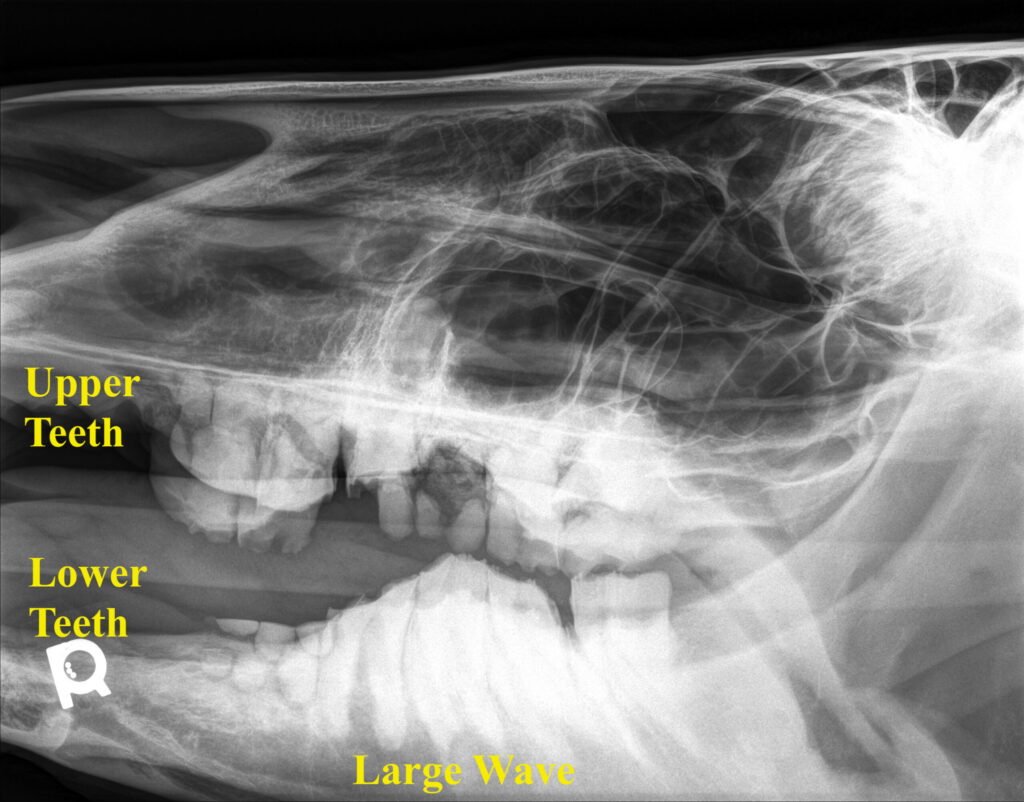

An example of malocclusion is “wave mouth” where the upper teeth contact the lower teeth at different heights, causing vertical misalignment that looks like a wave formation when viewed from the side of the mouth. Old horse teeth also carry a lifetime of wear and tear, which can lead to dental diseases like tooth fracture, deep dental cavities, and loss of the gum tissue and supporting bone (periodontal disease). Malocclusion can also lead to soft tissue ulceration. Wave mouth and dental disease can be painful and disrupt normal chewing and eating behavior in senior horses, which can lead to weight loss or an inability to maintain a healthy weight, particularly in the wintertime.